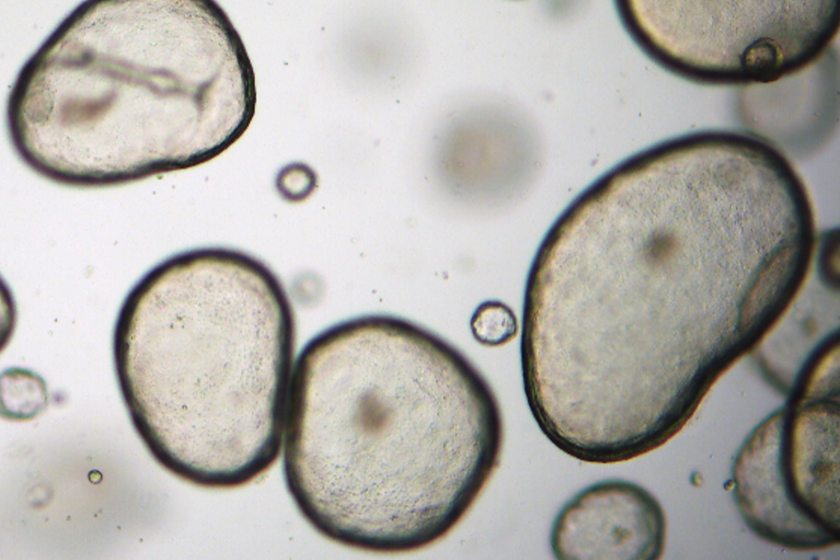

The Fugure of Biotech: Organoids

Application Note: Human Endometrial Organoids as a New Approach Methodology (NAM) for Preclinical Cytotoxicity Testing in Women’s Reproductive Health